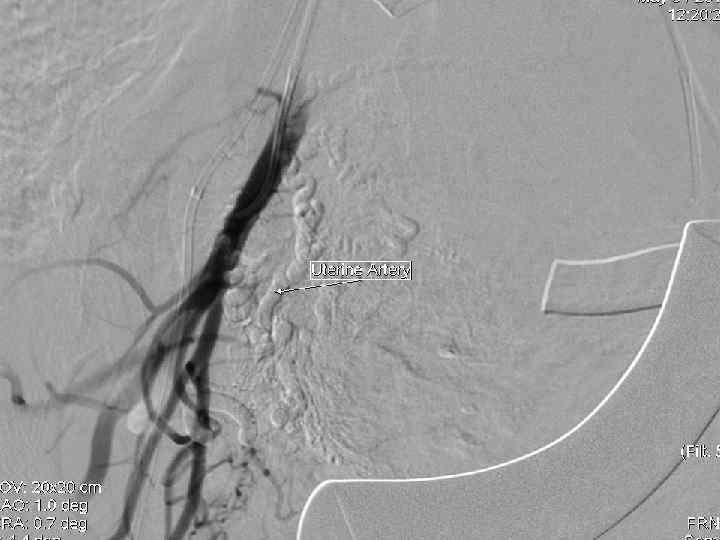

Эмболизация маточных артерий Показания к проведению ЭМА в акушерстве: - Высокий риск кровотечения в родах (предлежание плаценты, аномалии прикрепления плаценты, многоплодная беременность) - Гипо- и атонические кровоточения в раннем послеродовом периодах По данным литературы эффективность метода ЭМА при лечении акушерских кровотечений достигает 94, 9 %.

Эмболизация маточных артерий • - • Эмболизация проводится чрезкатеторной пункцией a. femoralis в верхней части бедра. Прокол осуществляется под местной анестезией. - В сосуд через интродъюсер вводят катетер, диаметром 1, 2 мм и проводят его под контролем рентгенотелевидения в маточные артерии. Продвижение катетера по сосудам безопасно и не вызывает никаких ощущений.

Эмболизация маточных артерий - • После установки катетера через него вводятся эмболизационные частицы. Среднее время продолжительности процедуры 15 -20 минут. В редких случаях особенности строения маточной артерии могут потребовать большего времени для установки катетера. - Операция проводится ангиохирургом.